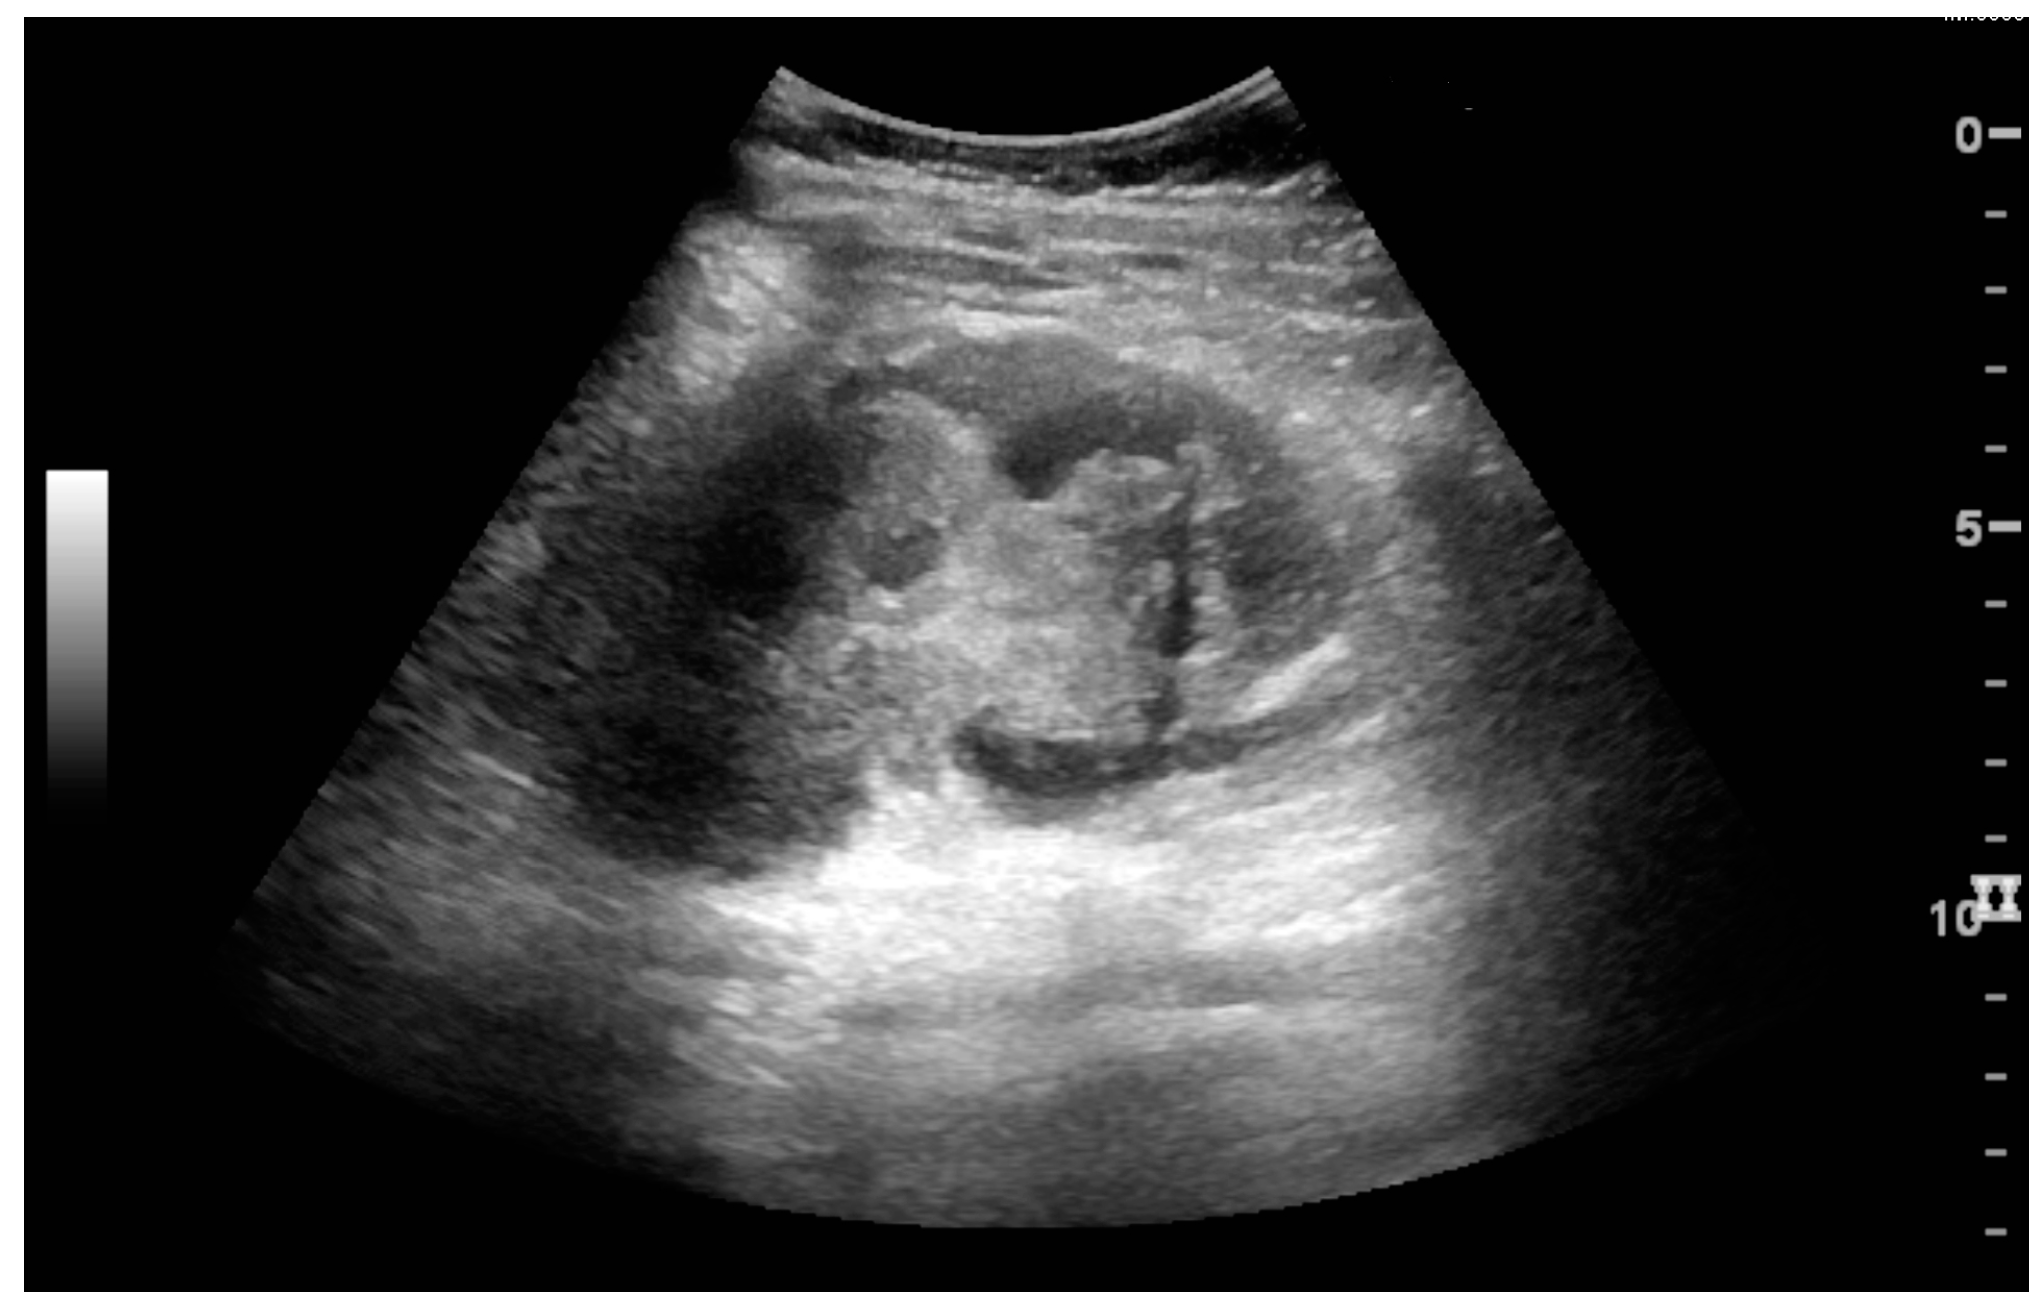

In polycystic kidney disease, multiple cysts of varying size in close contact with each other are seen filling virtually the entire renal region. In advanced stages of this disease, the kidneys are enlarged with a lack of corticomedullary differentiation (Figure 7) [17].

Figure 7. Advanced polycystic kidney disease with multiple cysts.